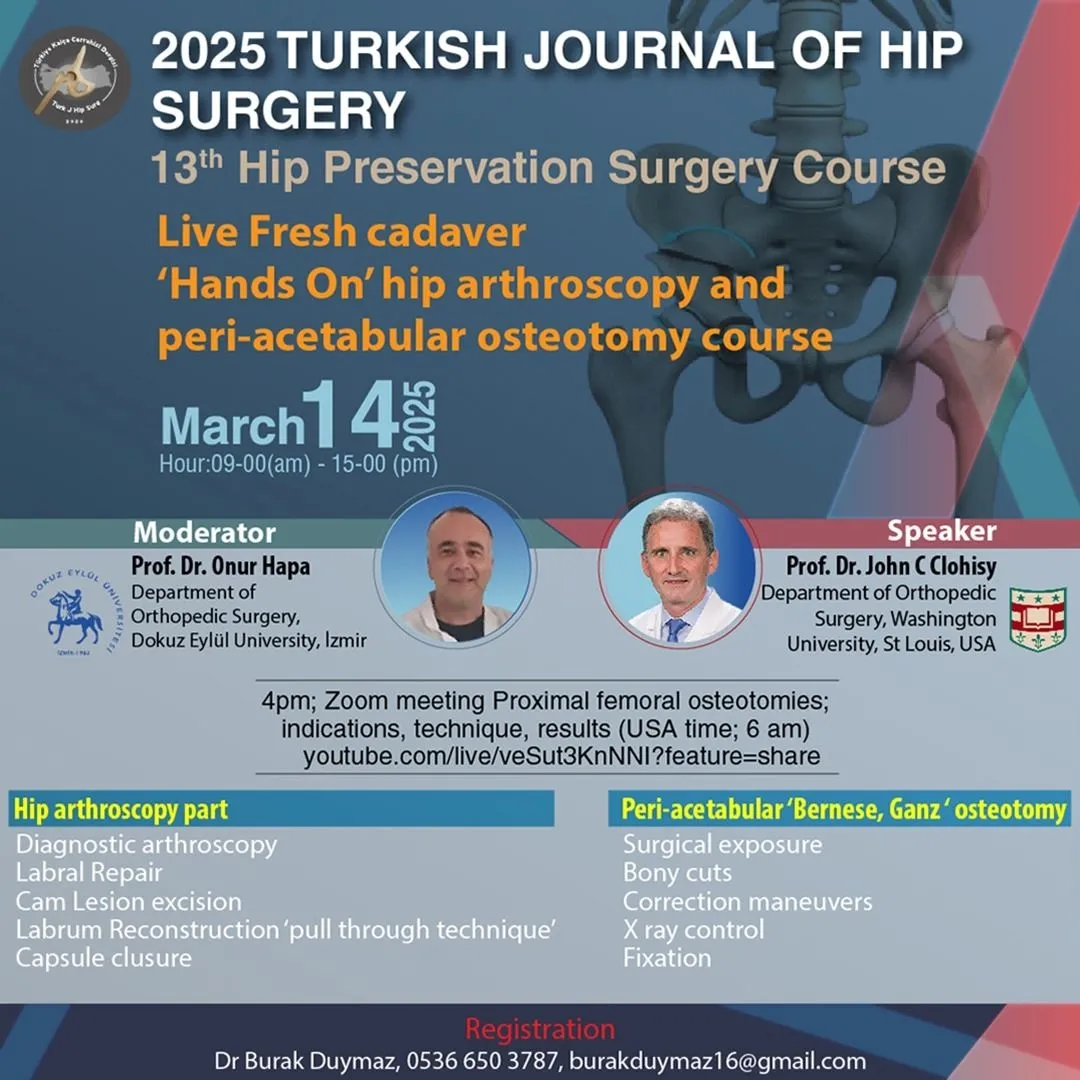

Live Fresh cadaver 'Hands On' hip arthroscopy and peri-acetabular osteotomy course

2024 Turkish Journal of Hip Surgery 11th Hip Preservation Surgery Course

2024 Turkish Journal of Hip Surgery 12th Hip Preservation Surgery Course

2023 TURKISH JOURNAL OF HIP SURGERY 10TH HIP PRESERVATION SURGERY COURSE

2023 Turkish Journal Of Hip Surgery 9Th Hip Preservation Surgery Course

2023 TURKISH JOURNAL OF HIP SURGERY 8TH HIP PRESERVATION SURGERY COURSE

Simultaneous hip arthroscopy and peri-acetabular osteotomy; When? How? - 15 Min Questions and Discussion - 10 Min